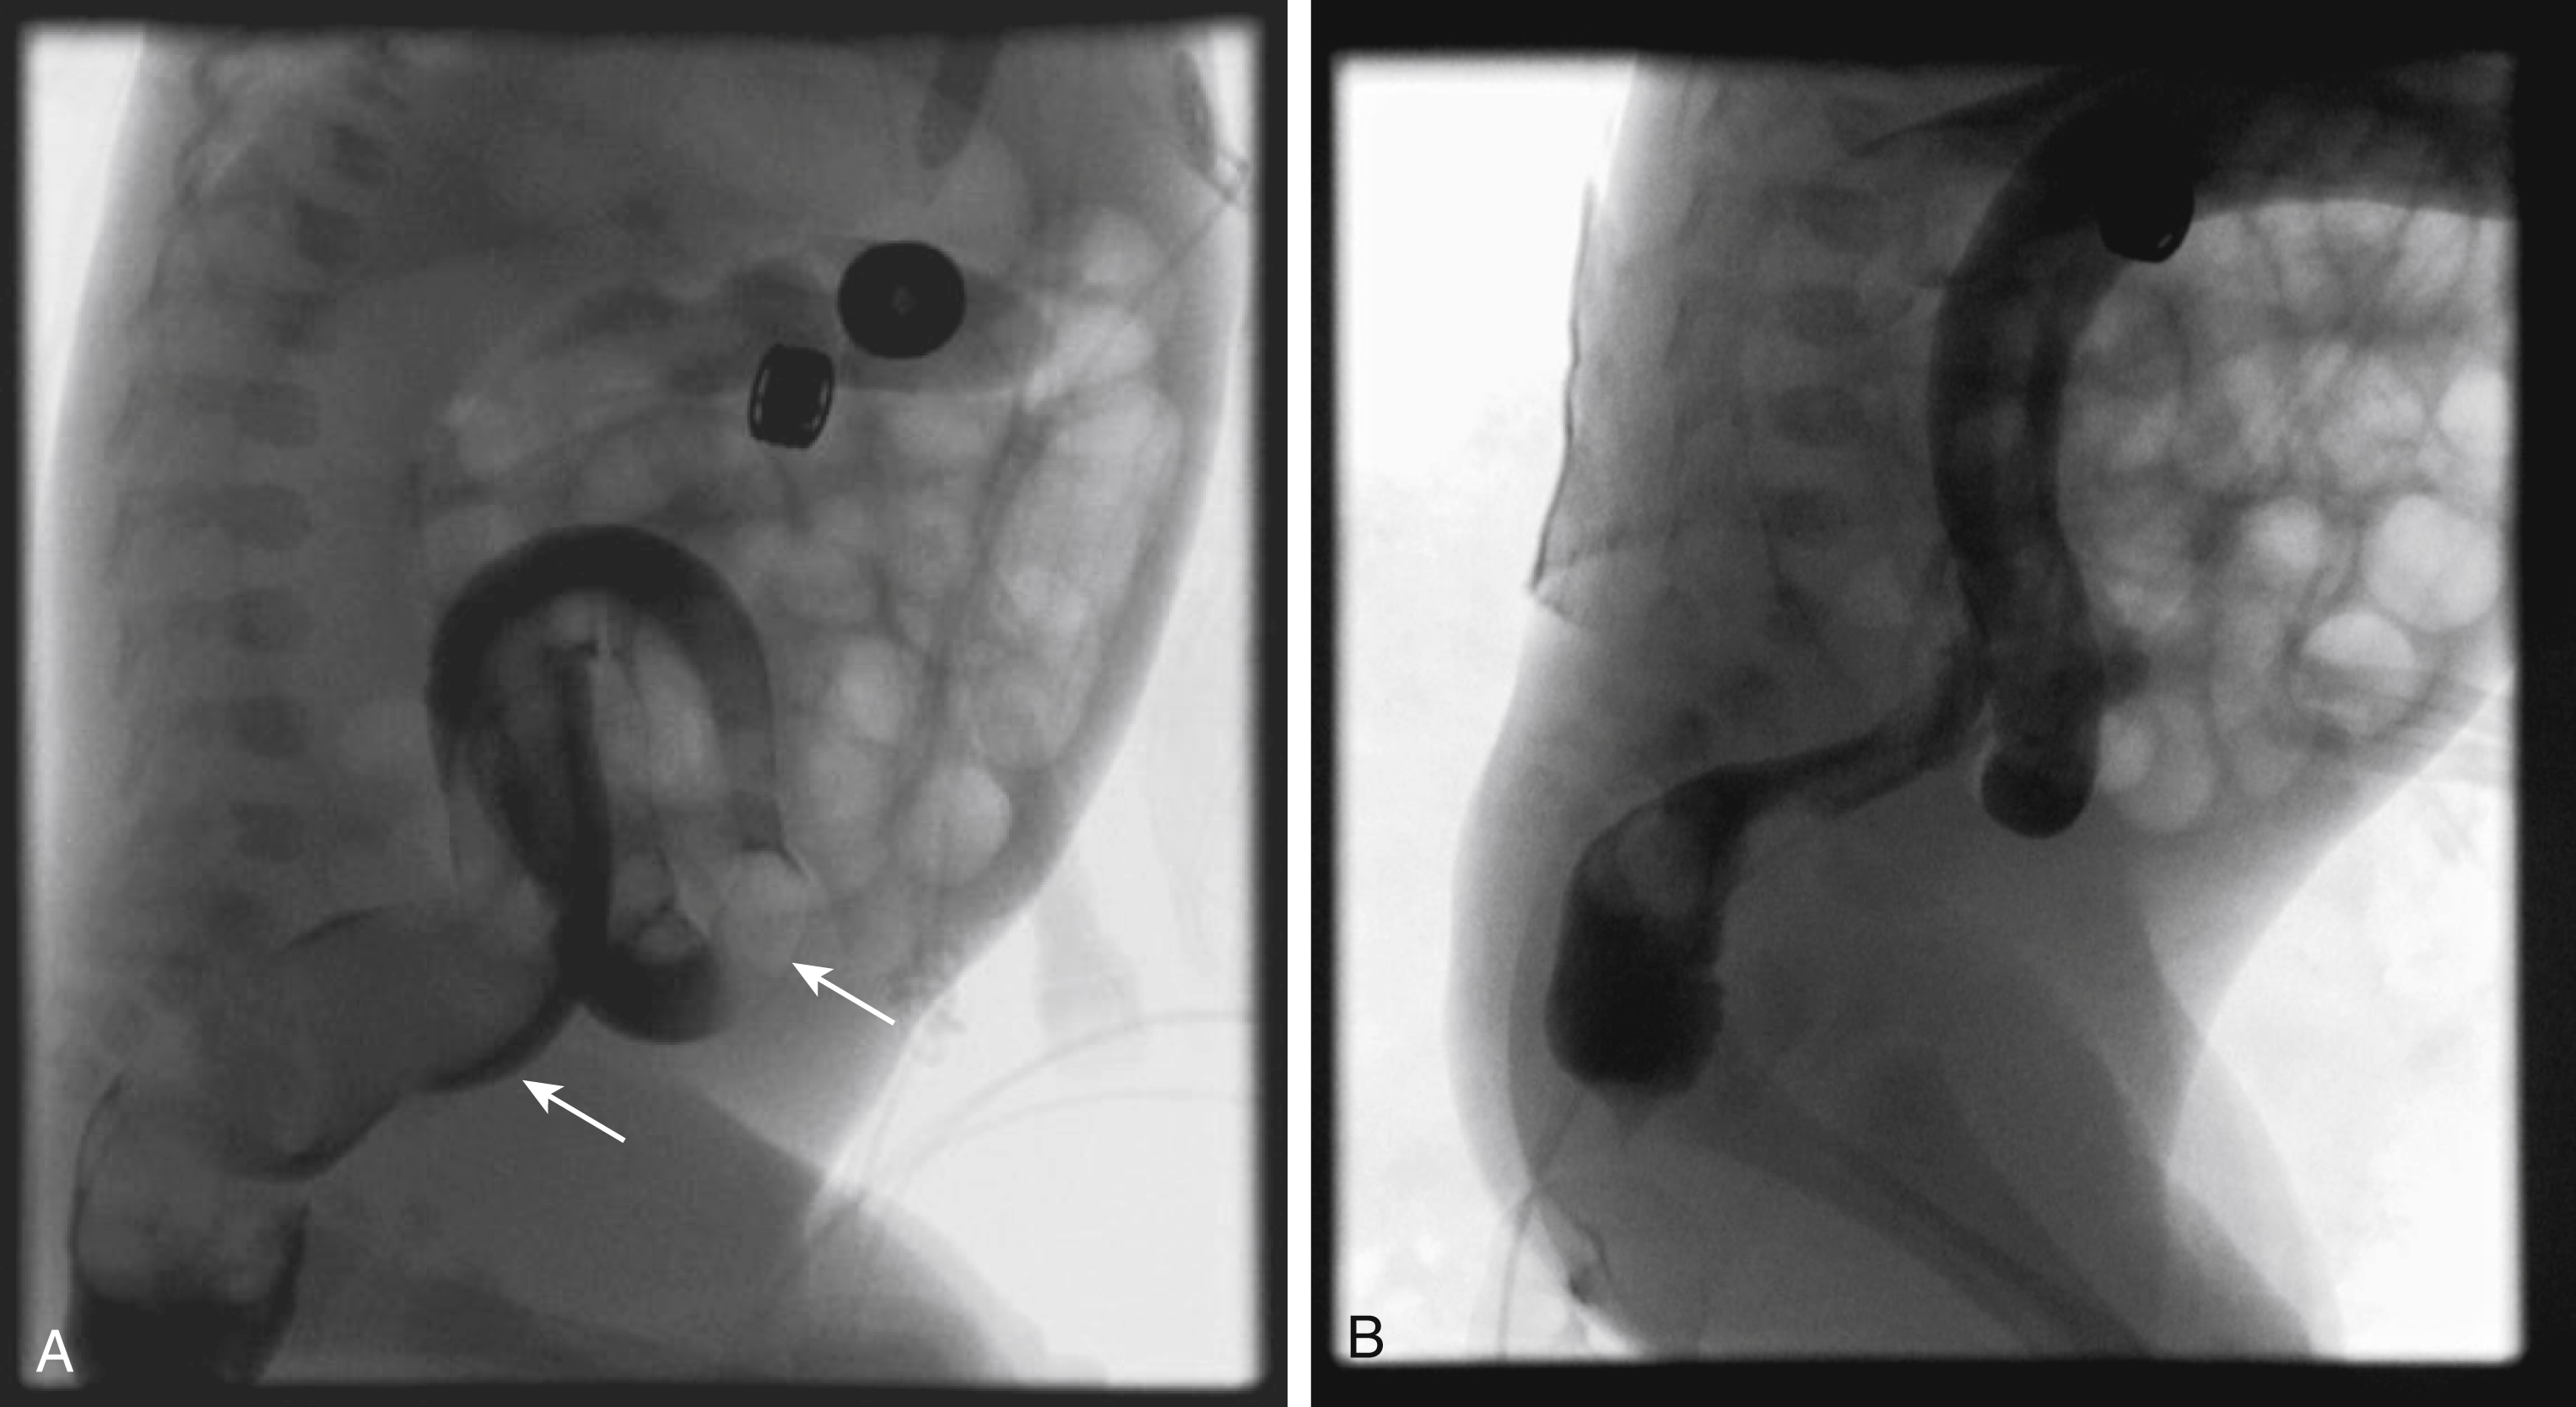

During fetal development, the midgut distal to the duodenum herniates into the umbilical coelom and rotates 270 degrees before reentering the abdomen. Subsequent fixation of the various mesenteries to the abdominal wall places the third portion of the duodenum in the retroperitoneum and positions the DJJ in the left upper quadrant and the cecum in the right lower quadrant, with a broad intervening mesentery along which the small bowel runs. Failure of this process can occur at different stages, leading to nonrotation or malrotation of the midgut, without a retroperitoneal duodenum. Depending on the final location of the DJJ and the cecum, the mesentery may therefore have a narrow attachment at its base. This narrow fan of mesenteric tissue is at risk for rotating around its central axis of the SMA and SMV. Such volvulus may obstruct the SMA and lead to bowel ischemia and even necrosis. In malrotation, the body forms fibrous attachments called Ladd bands , possibly in an attempt to fixate the gut. These usually extend from the cecum to the right upper quadrant and may cross the duodenum causing obstruction. The cecum may be located on either the right or left side of the abdomen and is normally located in 20% of malrotations. Imaging to assess malrotation focuses on the location of the duodenum. UGI documents position of the DJJ; on an UGI the normally located DJJ is at the craniocaudal level of the duodenal bulb lateral to the left spinous pedicles ( Fig. 4.1 ). Malrotation may be present without or with obstruction; obstruction may be caused by volvulus or a Ladd band ( Figs. 4.2–4.5 ).

Fig. 4.1, (Left) Normal duodenal–jejunal junction (DJJ): arrowhead indicates bulb; arrow indicates DJJ. (Right) Lateral view of DJJ at the level of the duodenal bulb.